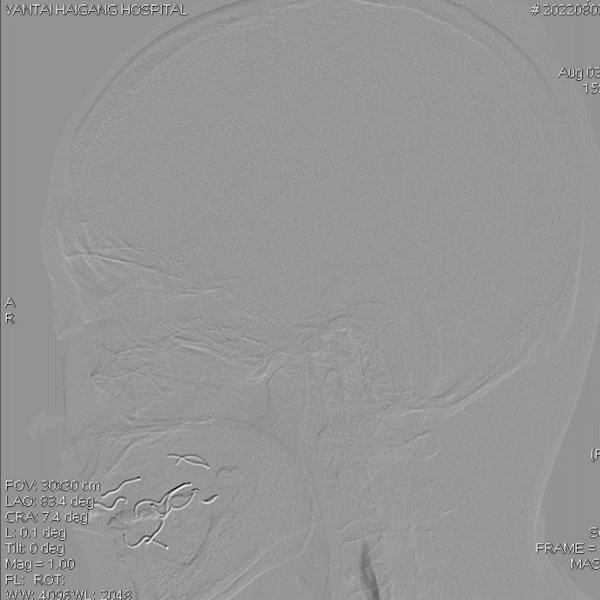

术后影像

术后即刻影像及患者术后情况:

造影见狭窄位置狭窄解除,支架贴壁良好,后循环各分支动脉显影良好。术后次日患者行走不稳情况明显改善,术后1月随访患者行走如常,未再发头晕。

术者体会

1. 患者右椎动脉开口与锁骨下动脉位置关系好,基本为垂直关系。故经右桡动脉建立治疗通路方便容易。

2. 患者后循环仅剩右侧椎动脉,同时V4段可见重度狭窄,为尽可能减少对血流的干扰,故尽可能选择管腔小一些的通路导管。

3. 病变处狭窄程度较高,为顺利通过支架,予以小球囊预扩张。

4. 赛诺神畅 颅内药物洗脱支架NOVA DES®顺应性较好,通过弯曲血管及病变处更顺畅,到位释放后横向支撑力好。其上雷帕霉素28天完全释放,有效降低血管再狭窄情况